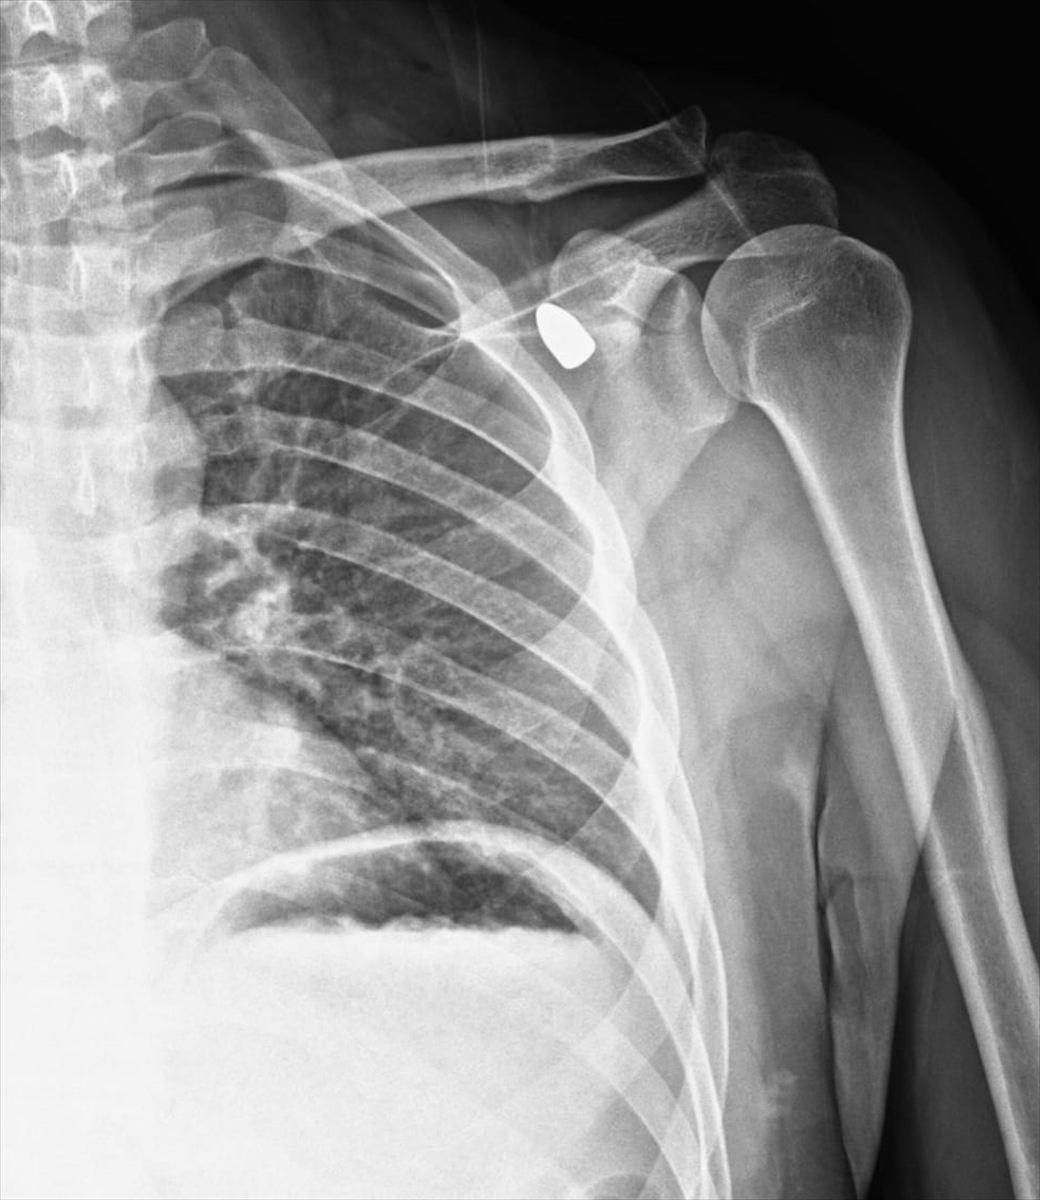

Konya'nın Akşehir ilçesinde altı yıl önce bir okul müdürünün omzuna isabet eden yorgun mermi tıbbi müdahaleyle çıkarıldı.

Okul müdürü Celal Şenyiğit, Adsız Mahallesi'ndeki çay ocağında, altı yıl önce omzuna isabet eden yorgun mermiyle yaralandı.

Hareket kaybı riski nedeniyle çıkarılamayan mermi, zamanla Şenyiğit'in koltuk altına ilerledi. Ağrı ve sertlik şikayetiyle Akşehir Devlet Hastanesine başvuran Şenyiğit'in koltuk altındaki kitlenin, omzuna saplanan yorgun mermi olduğu tespit edildi.

Mermi, gerçekleştirilen operasyonla çıkarıldı.